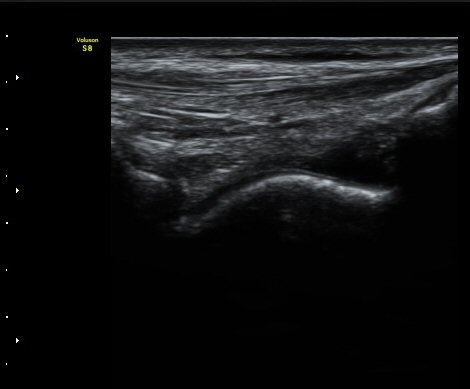

Àü°Å°ñºñ°ñÀδë Á¾´Ü¸é°Ë»ç¿¡¼­ ÀδëÀÇ ÀüÃþÆÄ¿­°ú ºÎÁ¾ÀÌ °üÂûµÈ´Ù(±×¸² 3, 4).

°ÇÃø(±×¸² 5)°ú ºñ±³ÇØ º¸¸é È¯ÃøÀÇ ÀÎ´ë ¼Õ»óÀÌ ¶Ñ·ÈÇÏ´Ù.

ÃÊÀ½ÆÄ Åõ½ÃÇÏ ºÎÇϰ˻翡¼­ ºñ°ñ°ú °Å°ñÀÌ ºñÁ¤»óÀûÀ¸·Î ¹ú¾îÁø´Ù(÷ºÎ µ¿¿µ»ó).